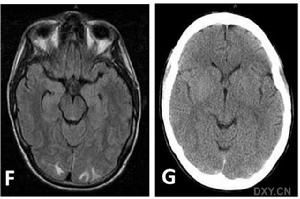

4.少數患者可有意識障礙精神異常及發熱;文獻報導過有失語、偏癱及一過性遺忘等有學者根據病因不同將其分為:原發性顱內低壓綜合徵;術後顱內低壓綜合徵;外傷後顱內低壓綜合徵;腰穿後顱內低壓綜合徵;及腰神經袖撕裂性顱內低壓綜合徵。體格檢查可有輕度頸部抵抗直立時心率減慢,神經系統常無陽性定位體徵腰穿檢查示腦脊液壓力低於70mmH2O,CSF常規化驗檢查多正常。CT或MRI示腦萎縮。以Gd-DTPA增強掃描MRI可顯示全腦硬腦膜瀰漫性強化腦垂直移位

二、輔助檢查:1.CT或MRI常顯示腦萎縮。以Gd-DTPA增強掃描MRI可顯示全腦硬腦膜瀰漫性強化腦垂直移位。2.前庭功能測定也有鑑別診斷意義